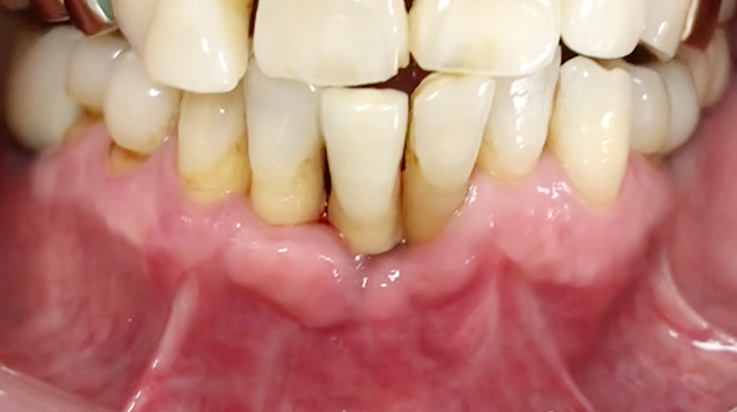

Crown lengthening (Anterior teeth)